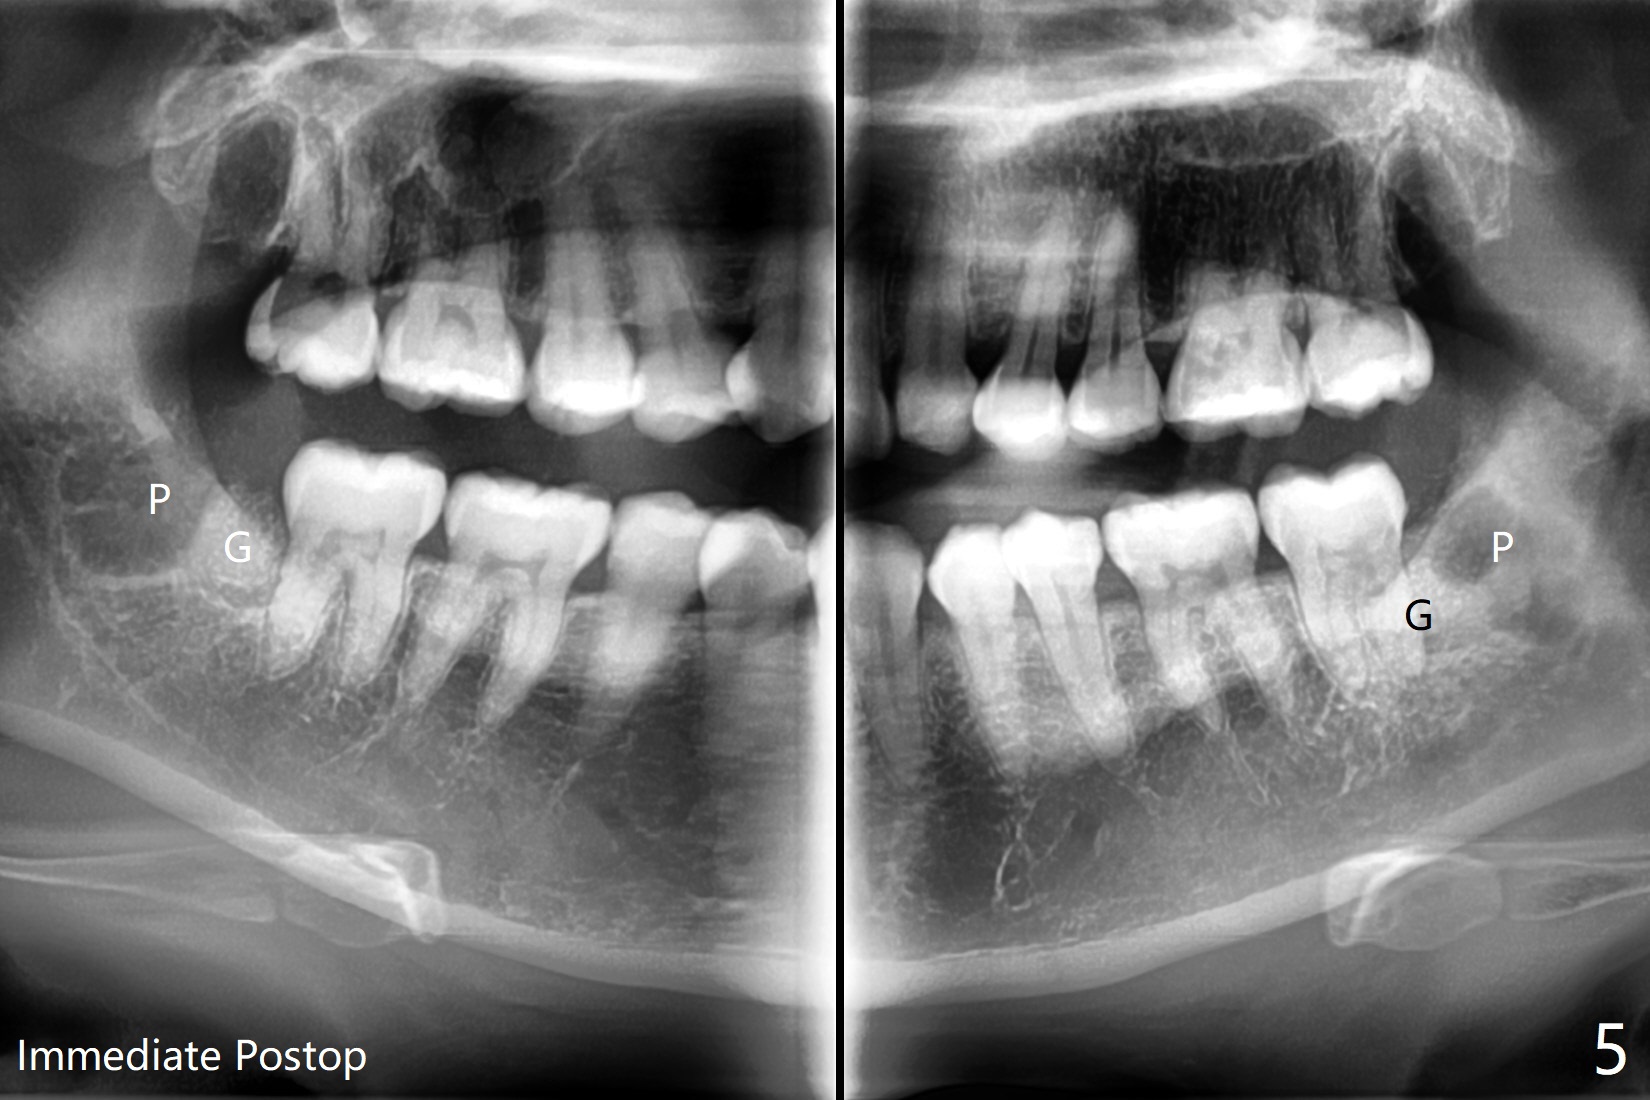

A 35-year-old timid woman finally decides to have 4 of the 3rd molars extracted (Fig.1). The apices of #17 overlaps with the Inferior Alveolar Canal (*). Small field CT shows that #17 is buccal to #18 (Fig.2), causing distal root exposure (Fig.3 D). In fact the buccal overlap seems to be more severe clinically (Fig.4) than what X-ray indicate (Fig.1,3). Therefore bone graft seems to be able to be packed mesially (Fig.5: G). In fact the left Inferior Alveolar Canal is exposed after extraction, collagen plug (P) is placed distal without use of curette around the exposed canal.